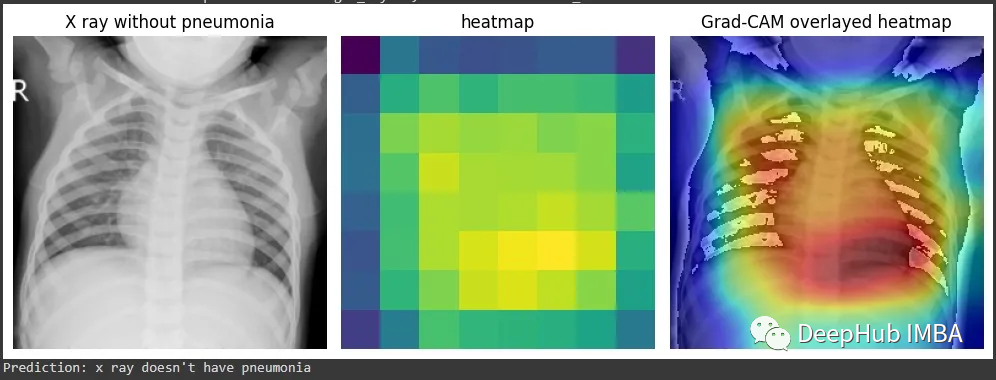

为了演示Grad-CAM的实现,我将使用来自Kaggle的胸部x射线数据集和我制作的一个预训练分类器,该分类器能够将x射线分类为是否患有肺炎。

得到的激活包含1024个特征映射,这些特征映射捕获输入图像的不同方面,每个方面的空间分辨率为8x8。通过钩子获得的梯度表示每个特征映射对最终预测的重要性。通过计算梯度和激活的元素积可以获得突出显示图像最相关部分的特征映射的加权和。通过计算加权特征图的全局平均值,可以得到一个单一的热图,该热图表明图像中对模型预测最重要的区域。这就是Grad-CAM,它提供了模型决策过程的可视化解释,可以帮助我们解释和调试模型的行为。

但是这个图能代表什么呢?我们将他与图片进行整合就能更加清晰的可视化了。

这样看是不是就理解多了。由于它是一个正常的x射线结果,所以并没有什么需要特殊说明的。

再看这个例子,这个结果中被标注的是肺炎。Grad-CAM能准确显示出医生为确定是否患有肺炎而必须检查的胸部x光片区域。也就是说我们的模型的确学到了一些东西(红色区域再肺部附近)